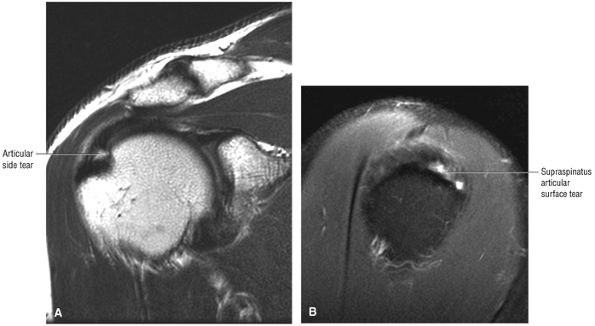

tendon tears and may result from fluid entering the muscle via a one-way valve mechanism through a partial-thickness tendon tear.